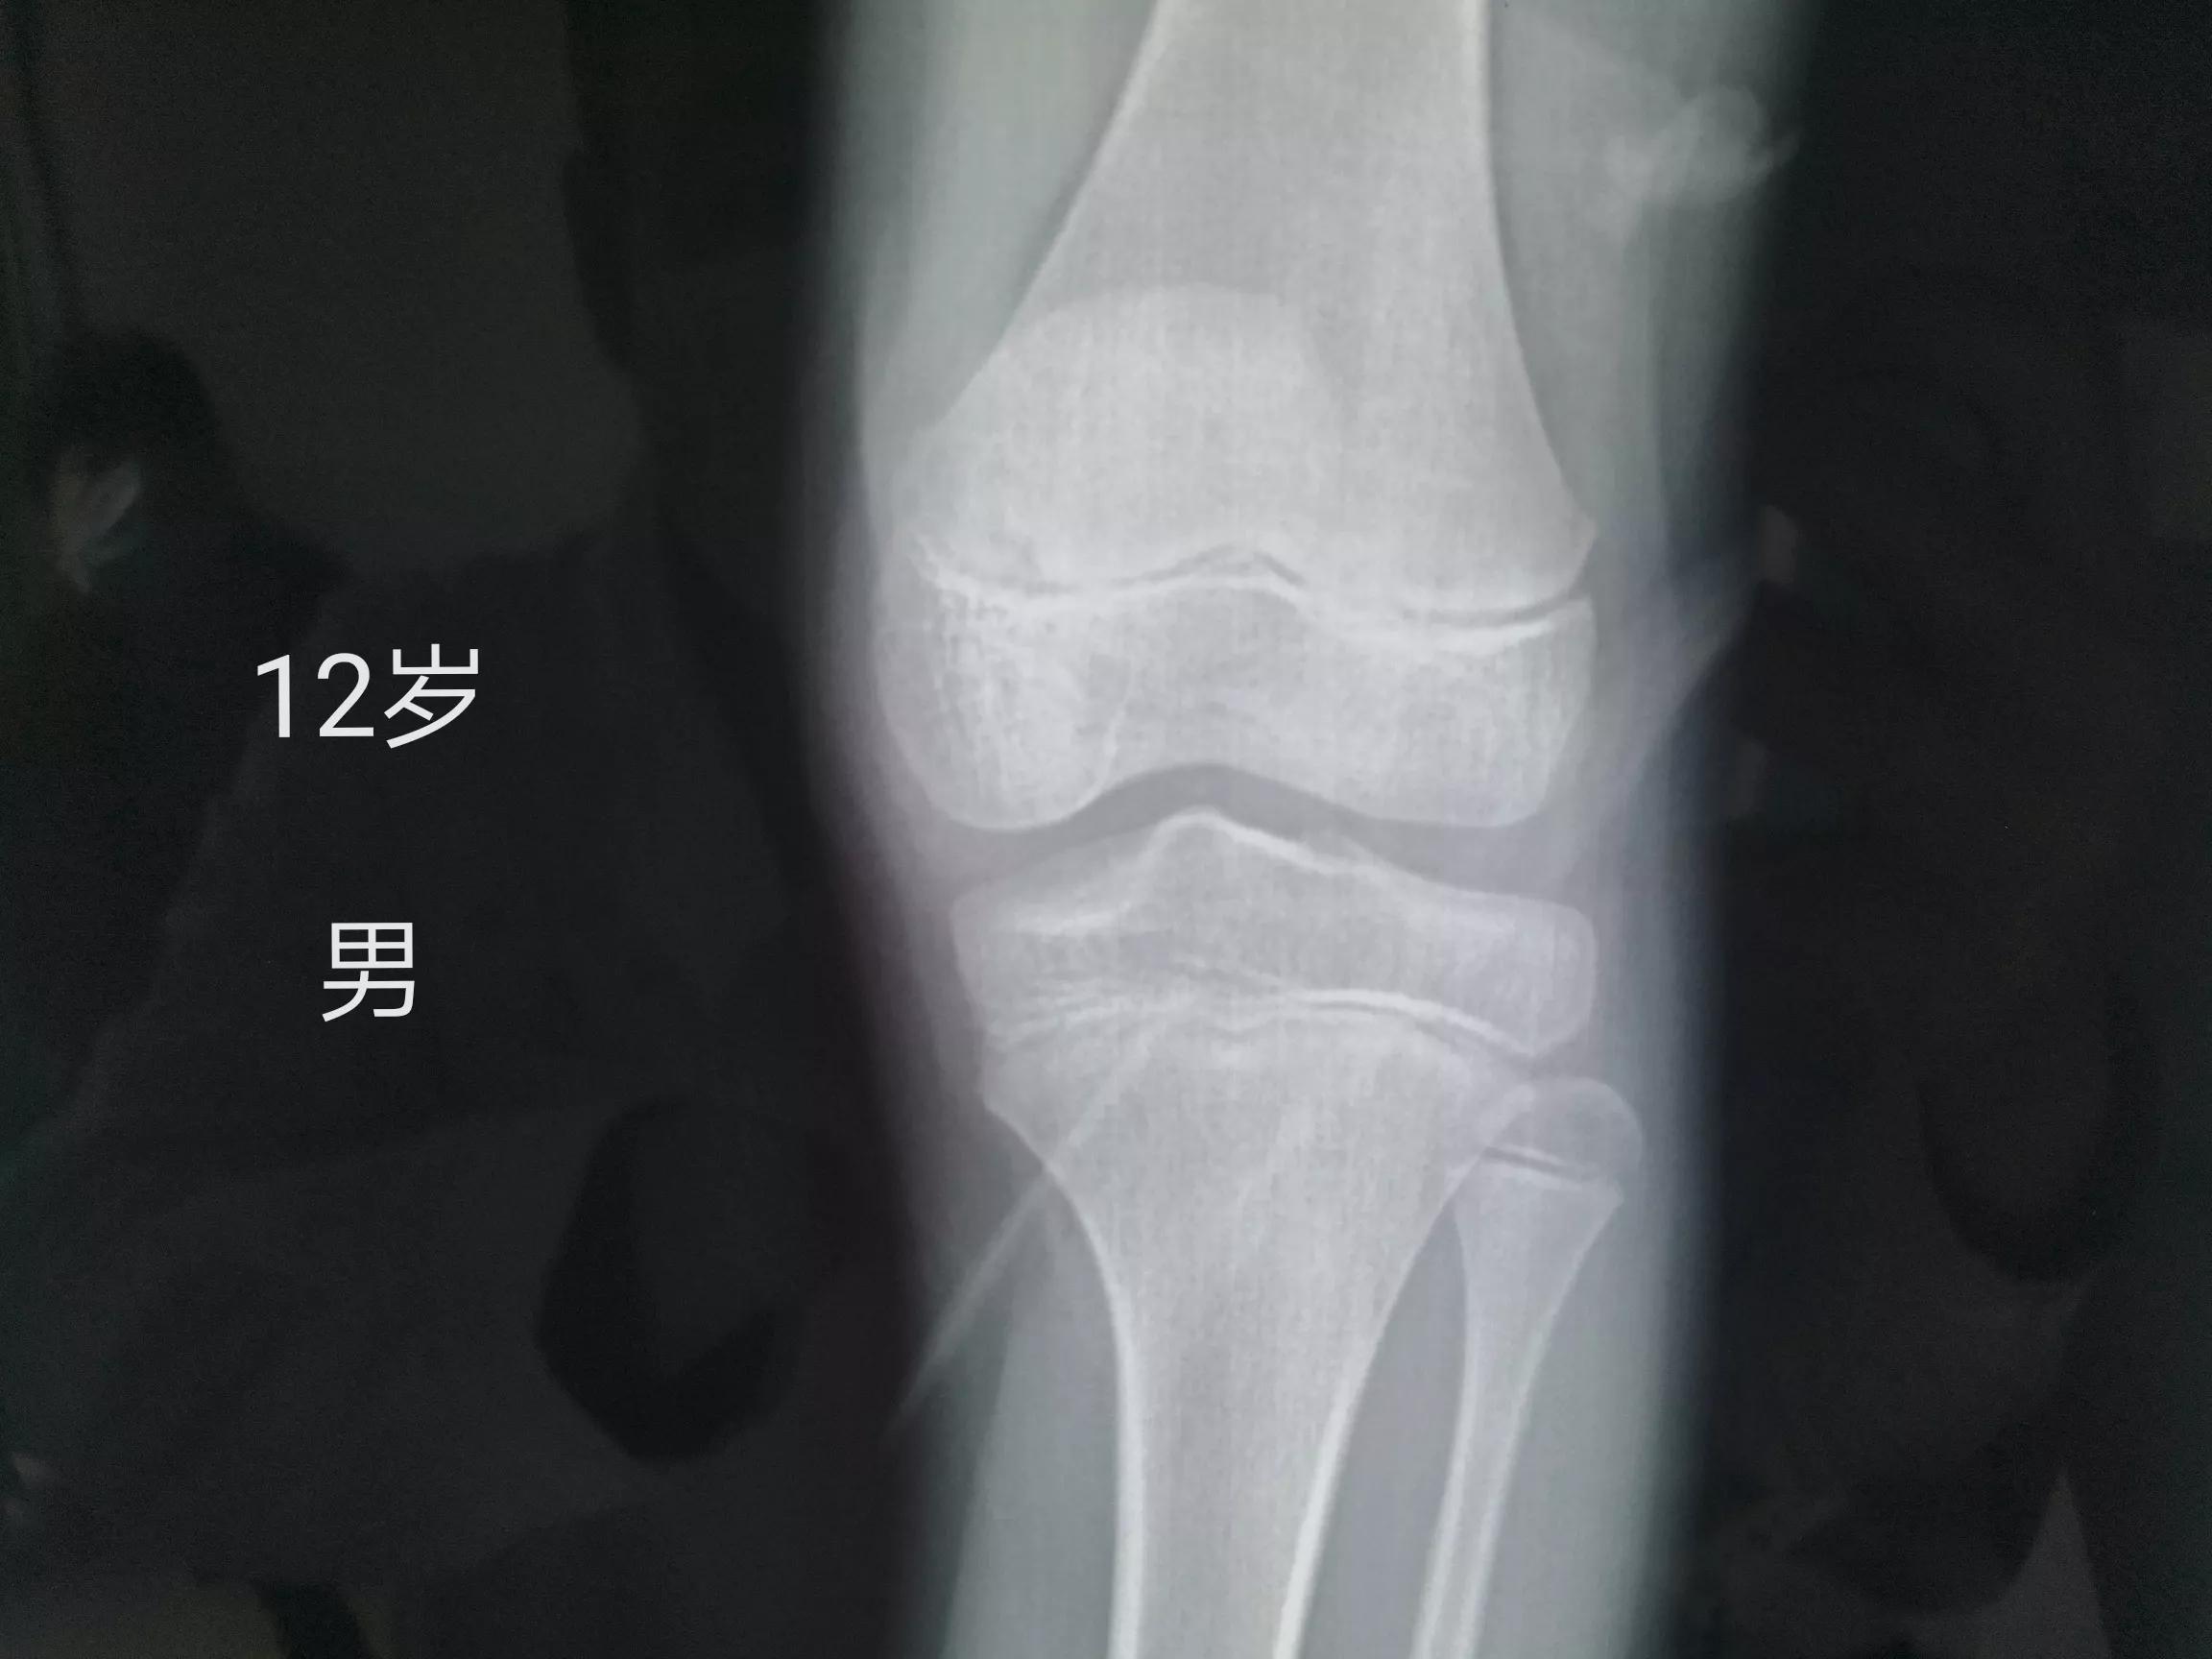

小孩子出现膝盖疼,通常会考虑两个问题,第一个就是生长痛,因为膝盖是有股骨的骨骺和胫骨的骨骺,在生长发育过快的时候,就会出现组织的牵拉,导致膝关节处的疼痛,所以在小孩子膝盖疼的时候,首先可以去给小孩子拍X光片,如果X光片没有什么明显的问题,就考虑是生长痛。